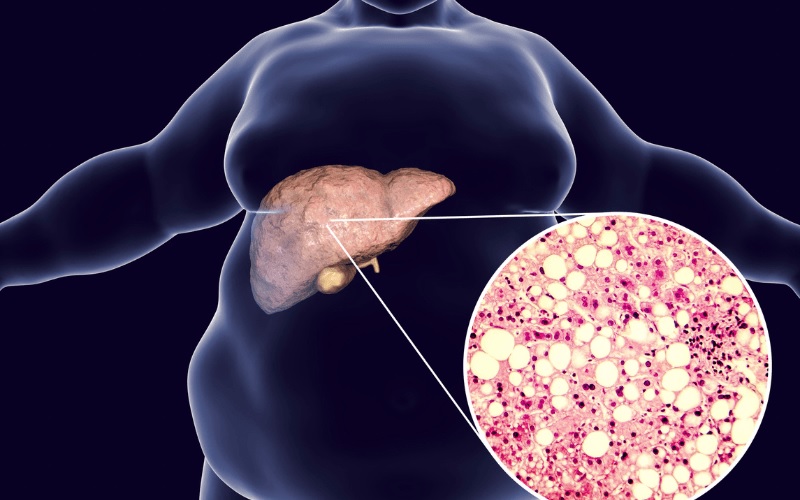

உடலில் உள்ள “சுத்திகரிப்பு நிலையம்” என்று சொல்லப்படும் கல்லீரலில், தேவைக்கு அதிகமாக கொழுப்பு தேங்கி சேரும் நிலையே கல்லீரல் கொழுப்பு சேர்வு நோய். ஆரம்பத்தில் அமைதியாக இருந்தாலும், காலப்போக்கில் இது “மௌனமாக முன்னேறும் பாதிப்பு” ஆகி கல்லீரல் செயல்பாட்டை குறைத்து விடும்.

சாதாரணமாக கல்லீரலில் சிறிய அளவு கொழுப்பு இருப்பது இயல்பு. ஆனால் அது அதிகரித்து, கல்லீரல் செல்களை பாதிக்கும் அளவுக்கு சென்றால், அது ஒரு நோயாக மாறுகிறது. இதை இரண்டு வகையாகப் பார்க்கலாம்:

இரண்டிலும் பொதுவான விளைவு: கல்லீரல் மெதுவாக பலவீனமடைவது.

இது “மெல்ல மெல்ல கல்லீரலை சிதைக்கும் நிலை” எனக் கருதப்படுகிறது.